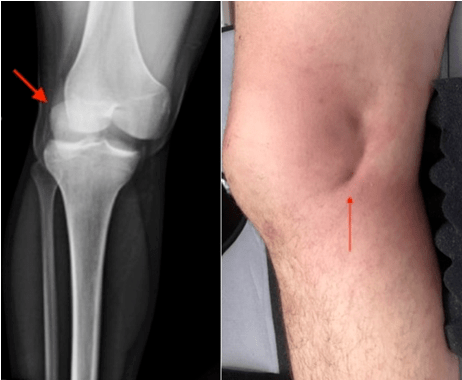

辅助检查:x线片:左膝关节脱位

膝关节脱位